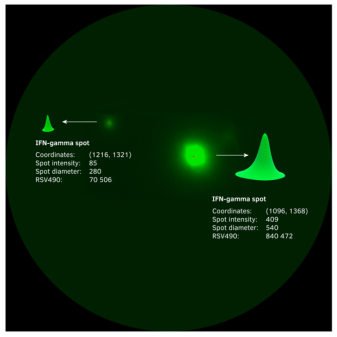

數據新的量度-Relative Spot Volume(RSV)

伴隨著現在數據信號處理能力的加強,采用革新化的RAWspot技術可以對每個斑點獲取其3D的體積,而該體積的大小與分泌因子的相對量呈正相關。這個針對新的斑點測量指標就叫做RSVRelative Spot Volume)。

每個斑點的三維體積與分泌物的相對量相對應,RSV的大小與細胞分泌因子的量呈正相關。